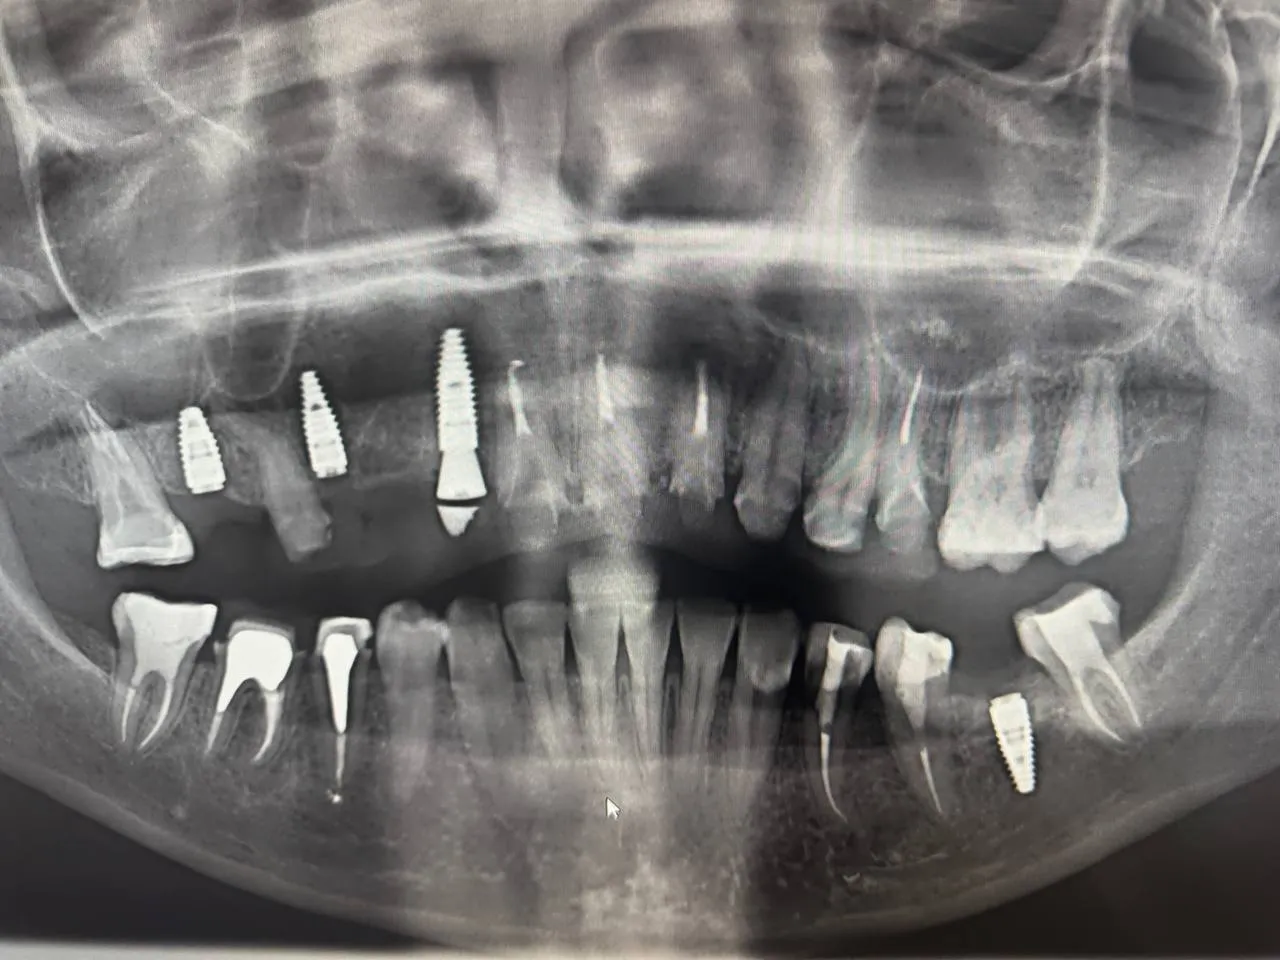

Maxillary Implant Case — 3 Implants

Tooth-supported guide for 3 implants in the upper jaw. Digital planning with precise implant positioning.

Dual Arch Rehabilitation — All-on-4 & All-on-6

Complete upper and lower jaw rehabilitation. All-on-4 concept for maxilla and All-on-6 for mandible with custom surgical guides.